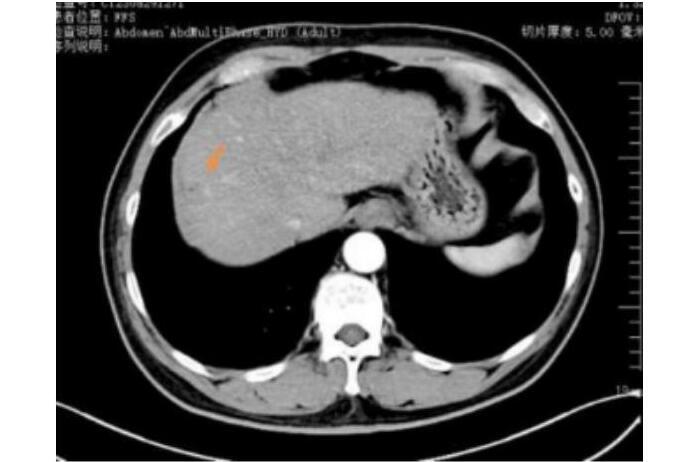

王先生(化名)65岁,2023年5月体检时发现肝占位,后行肝胆脾增强CT检查提示肝右叶富血供结节,径线约22mm*17mm,影像诊断考虑为肝恶性肿瘤,来到哈医大四院介入血管外科寻求进一步诊疗。患者行TACE术治疗后一周,接受了CT引导下冷冻消融治疗,术中患者疼痛轻微,术后患者恢复良好,三天后顺利出院。

术前上腹CT增强检查,考虑肝右叶恶性肿瘤